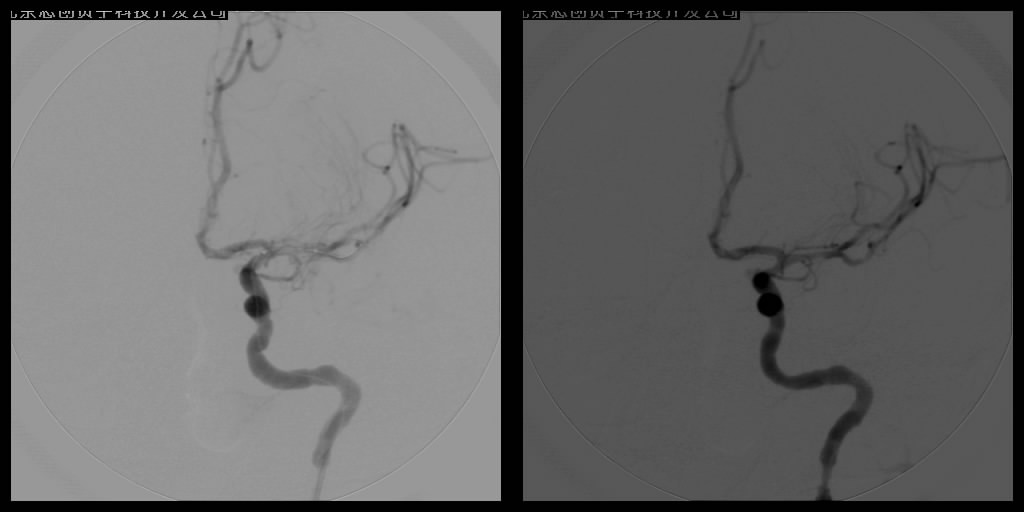

血管球囊扩张成形术和血管内支架植入成形术已经成为治疗脑缺血、脑梗塞十分重要的手段。手术操作时在DSA监控下,将导引管经主动脉插到供应颅脑的血管——颈动脉或椎动脉内,再置放支架,达到扩开狭窄段血管、顺性行血流再建的目的,所用支架可分为球囊扩张式支架和自膨式支架。DSA系统辅助下的动脉血管成形术不但能清晰明确地了解影像病变,而且在造影过程中就可了解血管内血流、血管壁等情况,全面判断血管结构及功能变化,为确诊和治疗提供了可靠的依据,已在临床上取得了良好的疗效。